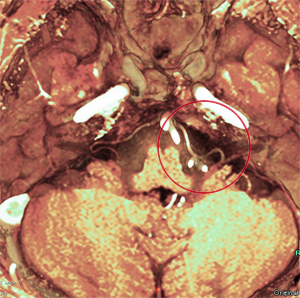

顔面痙攣・三叉神経痛

顔面痙攣・三叉神経痛についてはMRIで神経に血管の圧迫があるかをまず確かめます。症状を緩和する薬物療法でなく根治的治療を希望される場合は、神経血管減圧術を行います。治療効果や安全性が高まるような手技を心掛けています。

顔面痙攣で顔面神経に血管(白)が圧迫

立体的画像